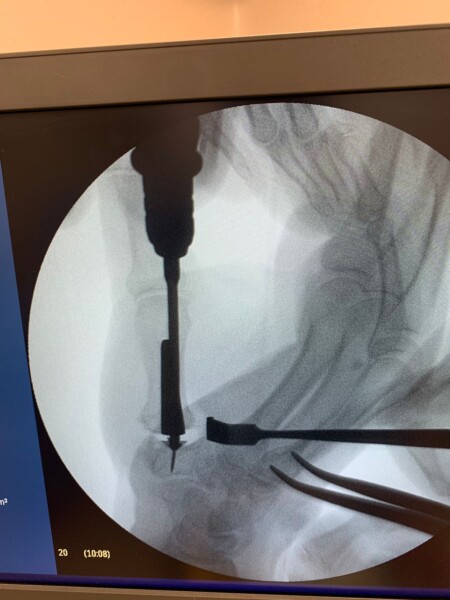

El médico, quien además es miembro Titular de la Asociación Argentina de Cirugía de Mano y Reconstructiva de Miembro Superior, explicó que la paciente se trataba de una mujer de 73 años, con una vida muy activa, que padecía de artrosis en la base del pulgar derecho, muy avanzada y con incapacidad funcional. Por ese motivo se decidió realizar una artroplastia con una prótesis total de la articulación carpo metacarpiana del pulgar ya que la misma le facilita una recuperación fácil, rápida y principalmente pasando el dolor en poco tiempo.

Dr. Juarez Cesca: La cirugía básicamente consiste en reemplazar la articulación de la base del pulgar, que es la articulación carpo metacarpiana del pulgar, por una articulación nueva, que sería la prótesis. Para ello, sacamos parte de los huesos y reemplazamos con la prótesis. La prótesis es exactamente lo mismo, como para que se pueda describir, es como una prótesis de cadera pero en el pulgar, hasta la forma es prácticamente la misma, nada más que otro tamaño y va en la base del pulgar.

Dr. Juarez Cesca: El material que tiene la prótesis es titanio y tiene un componente de hidroxiapatita que lo fija al hueso, es titano e hidroxiapatita, no lleva cemento para adherirse a la superficie. Todo esto de la hidroxiapatita hace que se vuelva rugosa la estructura, se fije y se asocie al hueso.